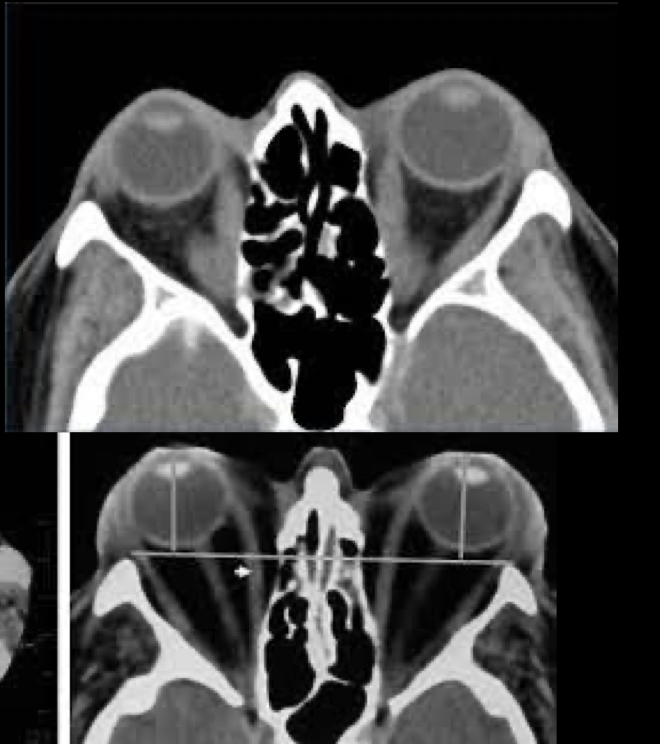

Q

A

TC en orbitopatia tiroidea

6